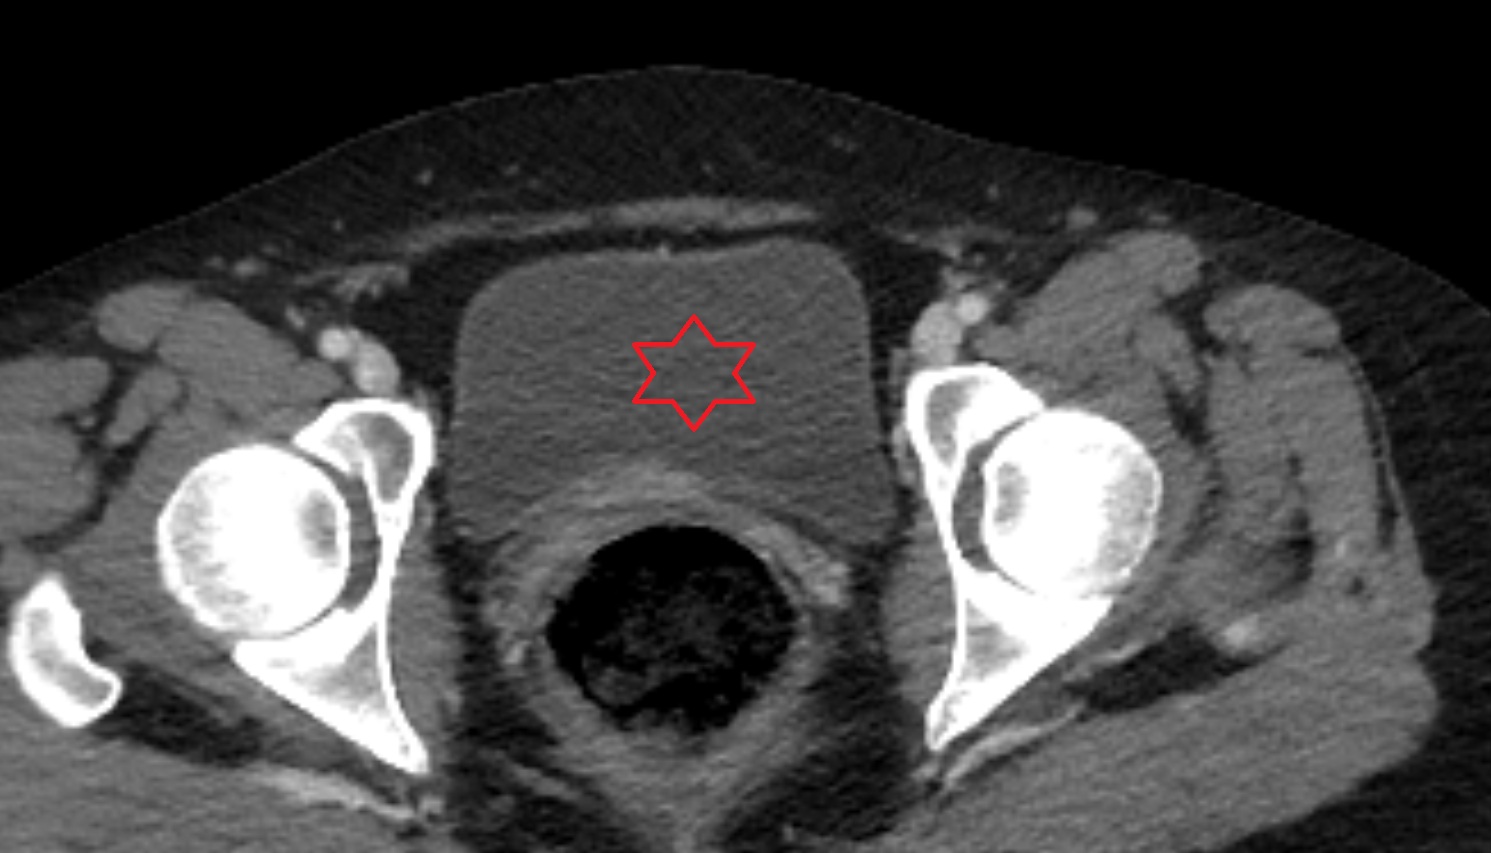

- Head of femur

- Acetabulum

- Acetabular margin (Acetabular rim)